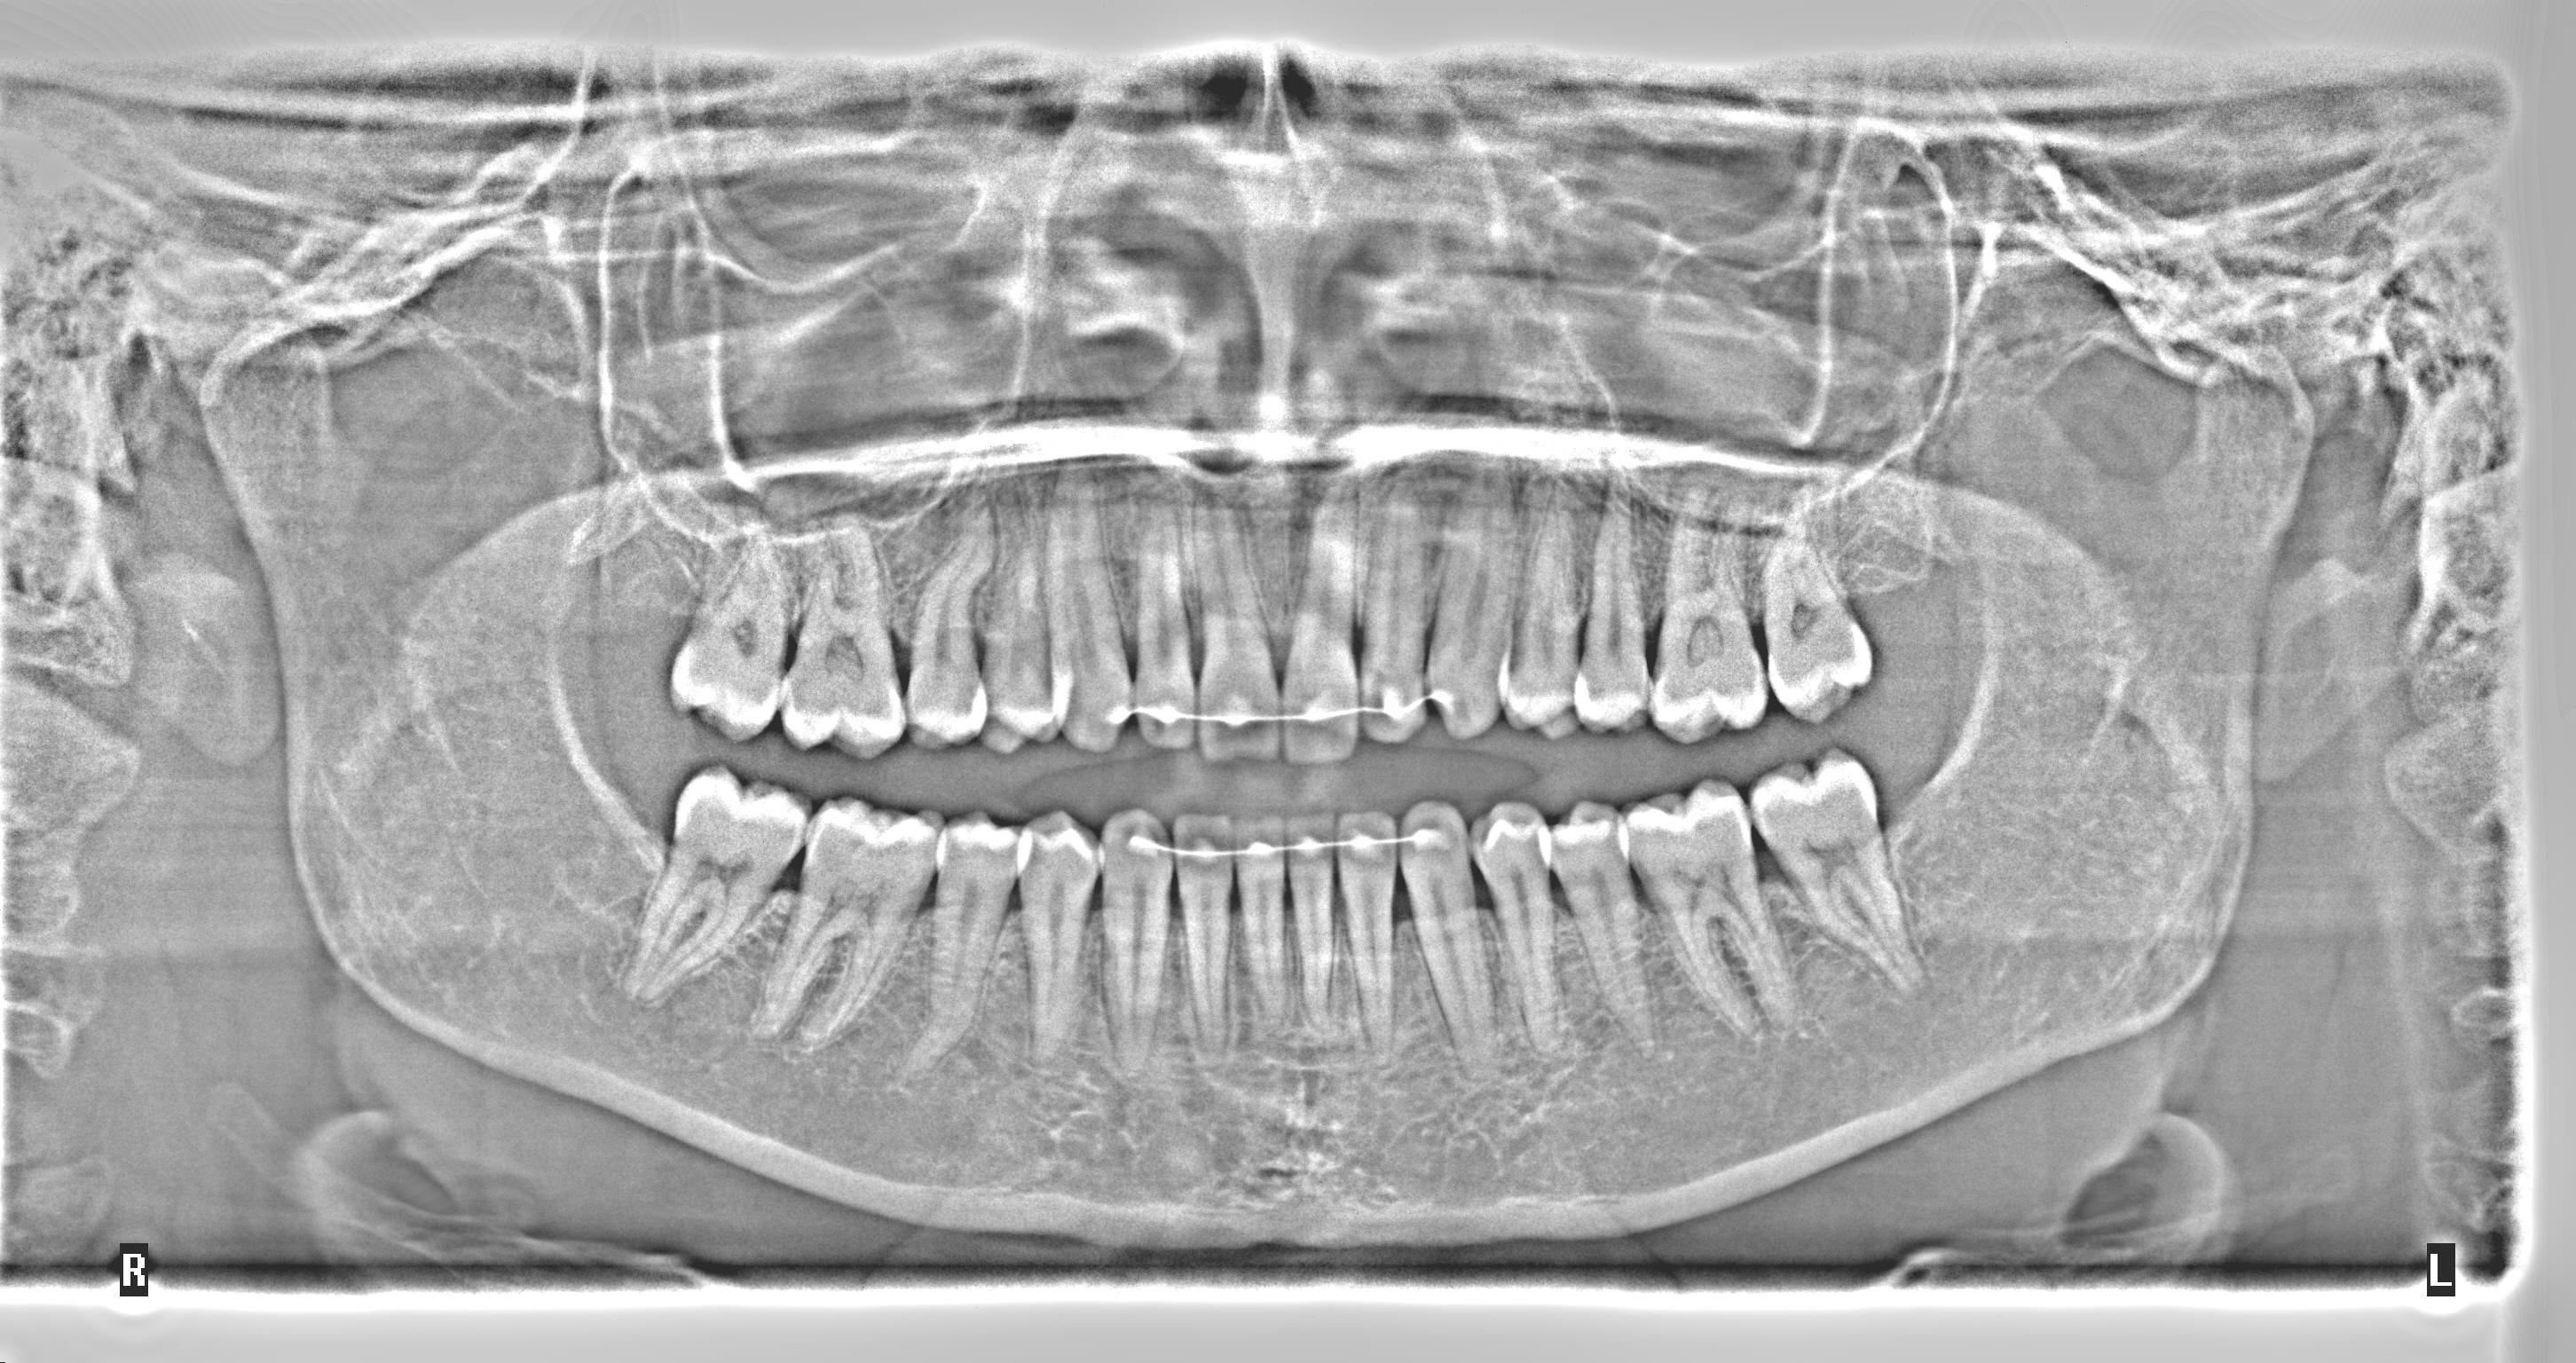

Methods: The clinical examination included extra-oral and intra-oral photographs, panoramic radiographic, lateral cephalometric, stone casts, and upper and lower arch analysis obtained from ClinCheck 3.0.The treatment planning was resolved the crowding in both upper and lower arches and the severe rotation of 33 tooth (46°) using Invisalign system as well as the canine and molar relationship, dental verticalization, adequate over jet, overbite and dental midline using the same system. The duration of the treatment was approximately eight months.

Results: In Post-treatment extra oralphotographs, no significant changes were observed at the end of the treatment. Intraoral photographs showed an important and notable improved aesthetics. The canine relationship improved slightly and molar Class Irelationship was maintained. An increase in transverse diameter was observed at the level of first premolars, second premolars and first molars. The overbite was improved. The crowding and the severe canine rotation were corrected. No obvious root resorption was radiographically evident and slight cephalometric changes.